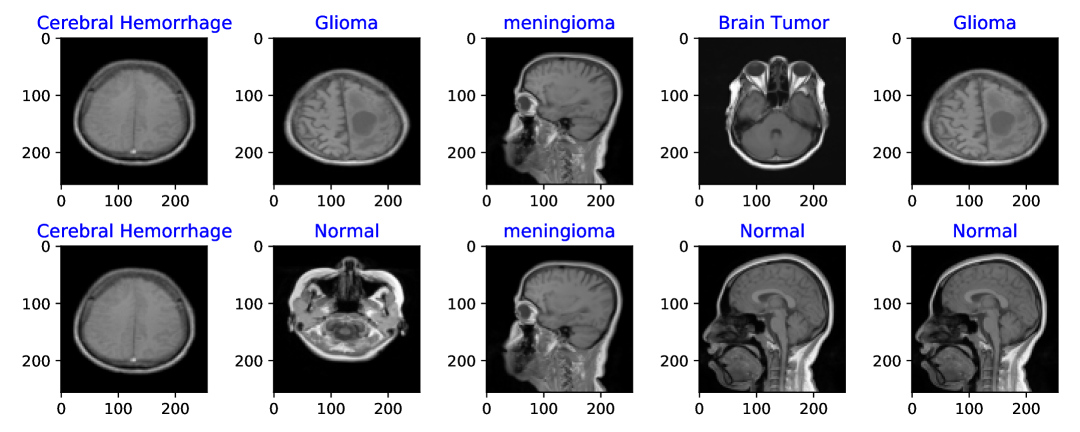

Refer to caption

Figure 1: Sample Images of the dataset.

This dataset is visually represented in Figure 1, which showcases a selection of random images from the dataset. These images are classified into 37 distinct categories. The extensive variety of categories in the dataset facilitates the creation of sophisticated diagnostic algorithms. This invaluable resource plays a crucial role in the training and validation of machine learning models that utilize computational techniques in medical imaging to enhance the precision and effectiveness of neurological diagnostics.